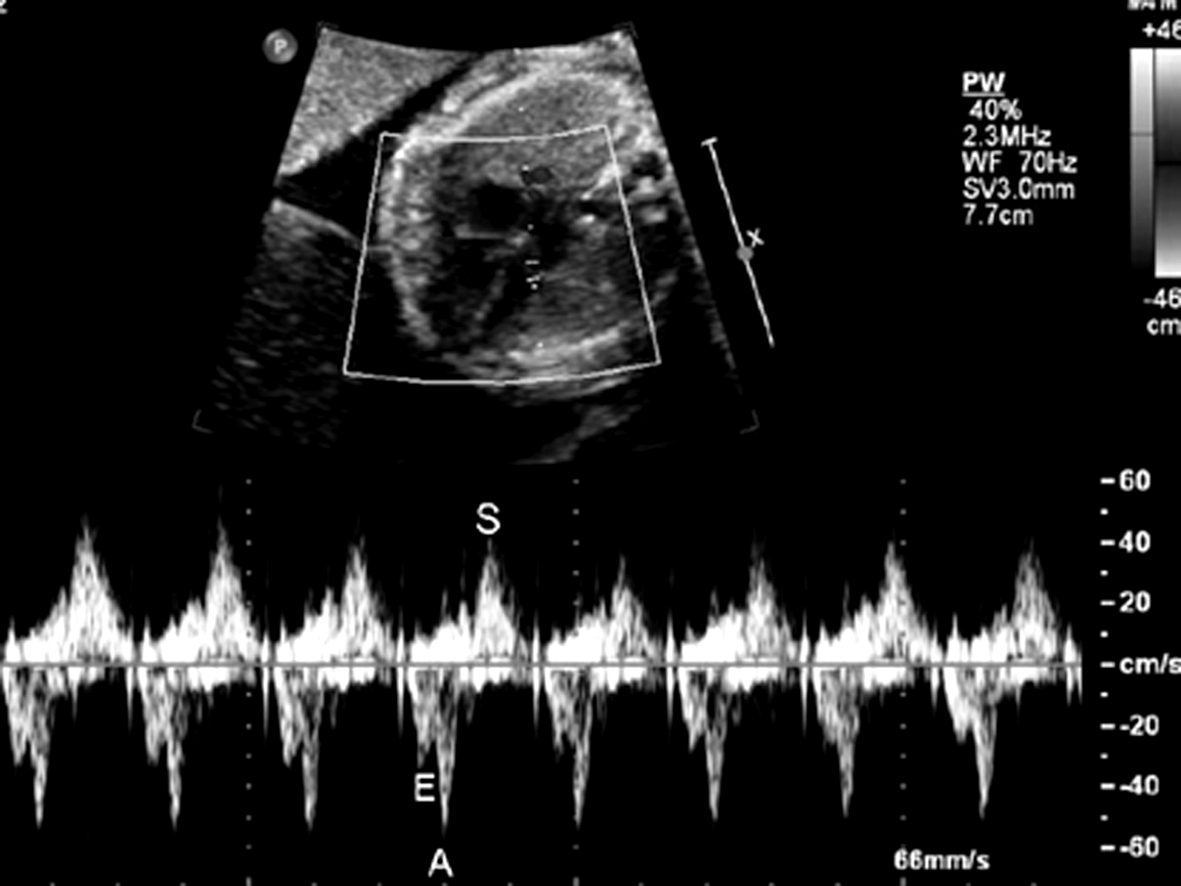

1.将取样门置于左室流入道和流出道交汇处,同时记录心室舒张期的二尖瓣(左室流入道)血流时间流速曲线和收缩期的左室流出道血流时间流速曲线,二尖瓣血流的A峰可反映心房的收缩期(图1)。此多普勒时间流速曲线关系反映了心房心室收缩的依从关系,当出现期前收缩或房室传导阻滞时,该依从关系发生改变。

图1 左室流入道、流出道血流时间流速曲线:E峰、A峰代表心脏舒张期,S峰代表心脏收缩期